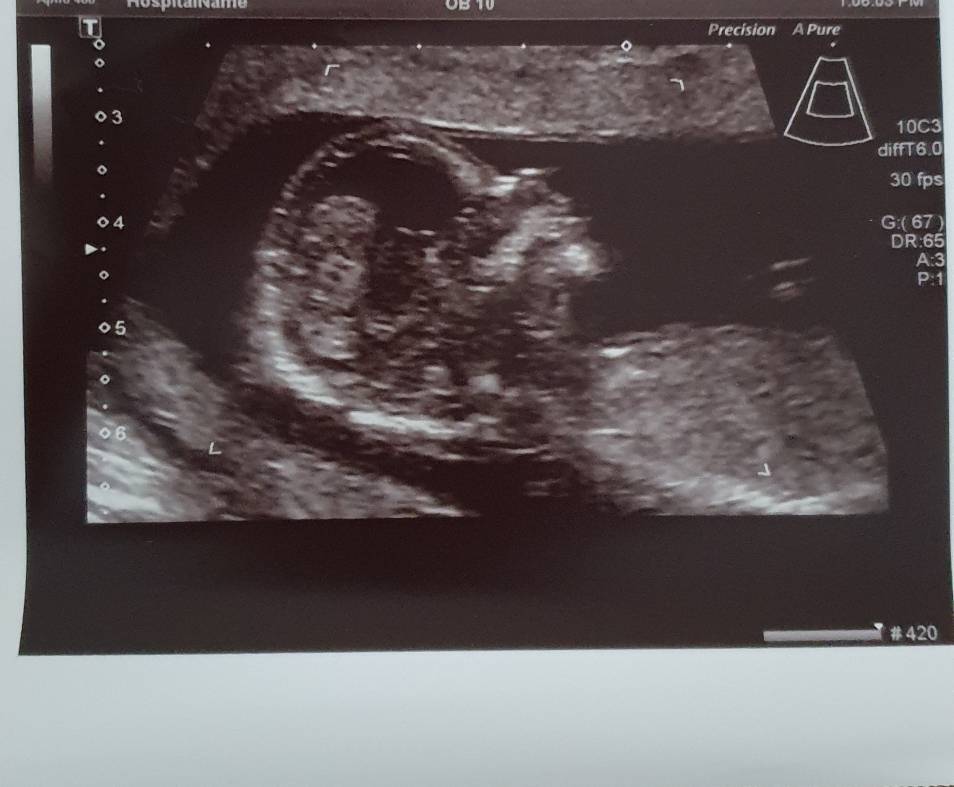

Hej jestem już po USG. Dziecko pięknie urosło do 3.71cm[emoji3059]. Wszystko dobrze, machal rączka, serduszko pięknie biło. Zero zastrzeżeń. Jedynie co to miesniak, urósł już do 8cm[emoji26] ale jest w miejscu gdzie nie powinien przeszkadzać dziecku i ból brzucha to przez to G...no[emoji35]